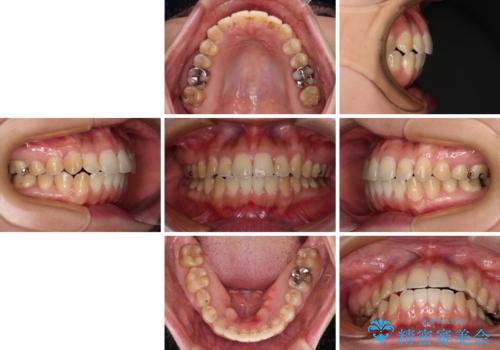

舌突出癖による開咬 舌のトレーニングを行いながら咬み合わせを改善

デコボコはあっという間に改善されましたが、開咬の改善に時間がかかりました。

舌の突出癖改善のトレーニングをしっかりと行っていただき、上下前歯が接触する咬み合わせを達成することができました。